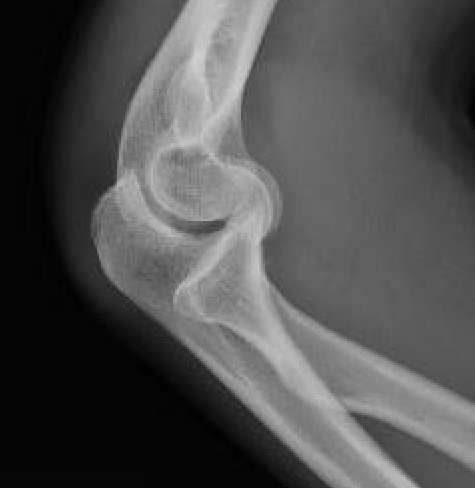

Coronal shear fracture of the distal humerus

Capitellum +/- trochlea

Bryan & Morrey Classification

| Type I | Type II |

|

Large osseous fracture of the capitellum

Articular cartilage injury with little bone |

Hanh Steinthal fracture

Kocher Lorenz fracture |